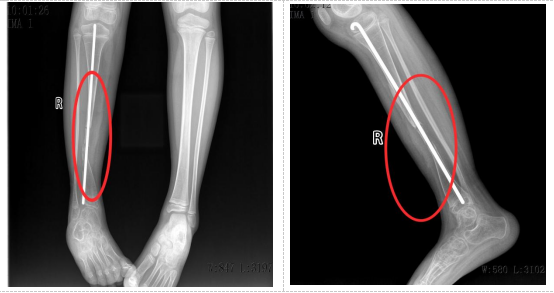

术前

小小出生3个月时即发现右小腿下段弯曲,2岁时因胫骨骨折辗转于数家医院,经多次手术失败后经人推荐来湖南省儿童医院治疗。先天性胫骨假关节导致小小右侧胫骨出现大段骨缺损,传统治疗方法效果有限,且存在肢体短缩、畸形甚至截肢的风险。面对这一棘手难题,湖南省儿童医院骨科团队经过多次病例讨论和精密规划,决定实施一项新的手术方案:“右侧胫骨内固定取出,右侧胫骨假关节病变切除,取左侧带血管蒂的腓骨移植,克氏针髓内固定,伊氏架外固定,左侧胫腓骨远端融合,石膏托外固定术”。即从小小健康的左侧小腿取一段带血管蒂的腓骨,移植到右侧胫骨缺损处,通过吻合血管重建移植后的腓骨血运,重建胫骨的完整性与支撑功能。